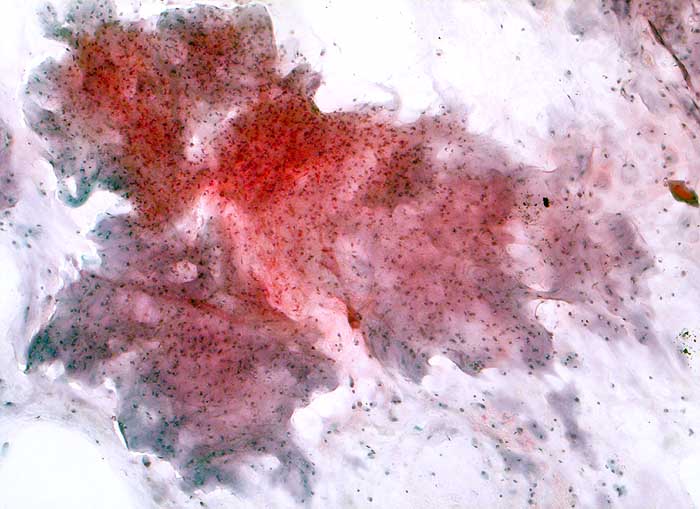

Chondrosarkom

maligner Tumor

Bronchialsekret

Lunge, Mediastinum mit Thymus

Bronchialsekret: Reichlich wolkige Matrix. Die einzeln in der Matrix eingebetteten Chondrozyten sind zahlreicher als in normalem Knorpel.

Histologische Diagnose: Ueberwiegend hoch differenziertes Chondrosarkom (Chondrosarkom Grad I bis II) der rechten Thoraxwand mit Infiltration der dorsalen, pulmonalseitigen Resektionsfläche

Brustwandtumor parasternal rechts Teils extra-, vorwiegend intrathorakal

Zytologie

50